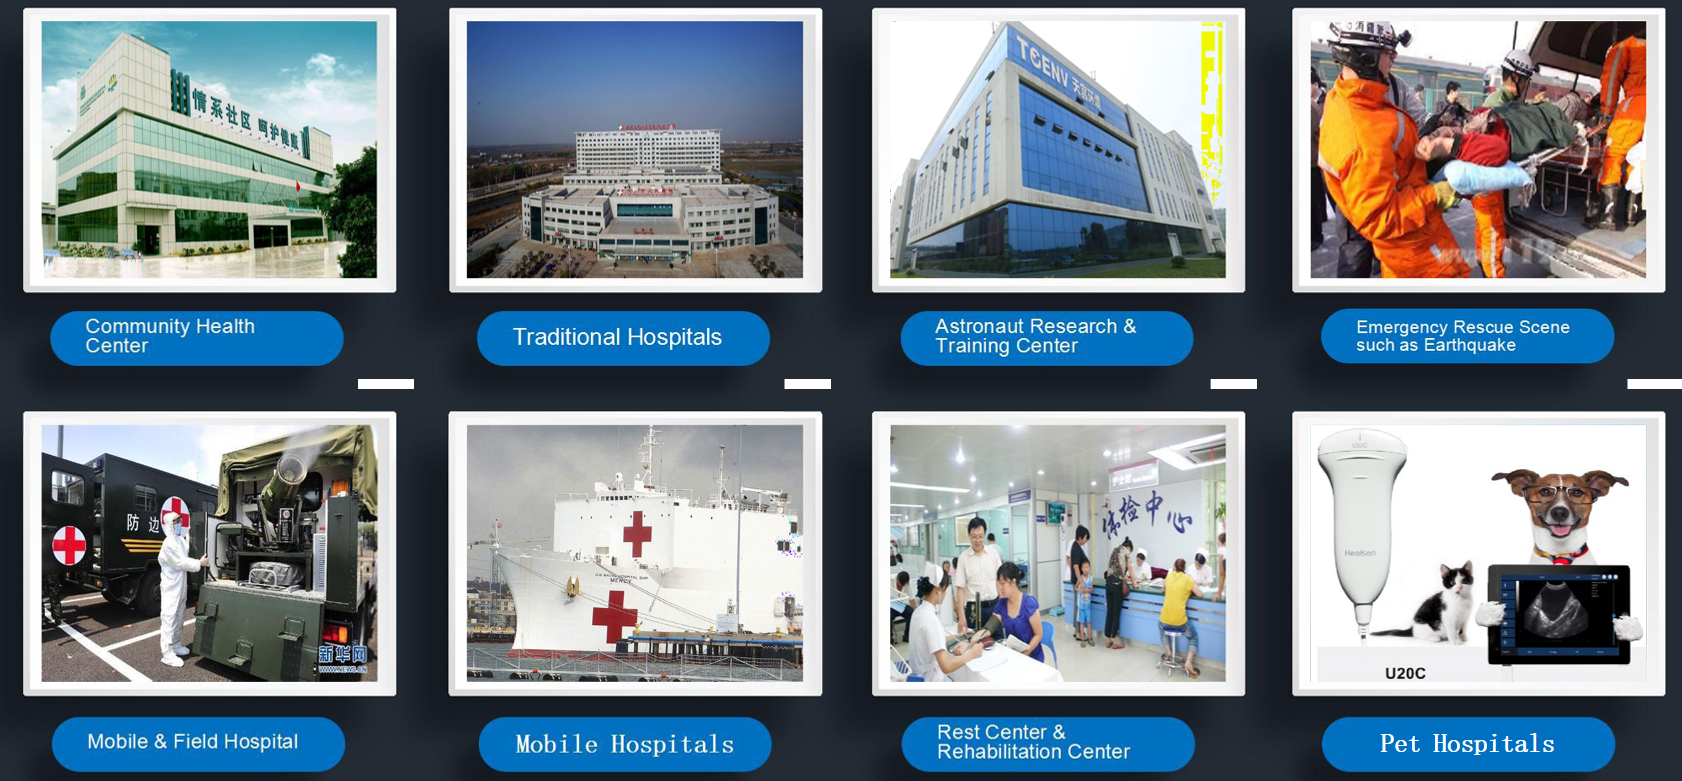

Product Application

i50 has excellent performance and different applications according to user's demands: Gynecology, Obstetrics, Abdomen, Urology, Vascular, Small parts, Orthopedic, Interventional etc.